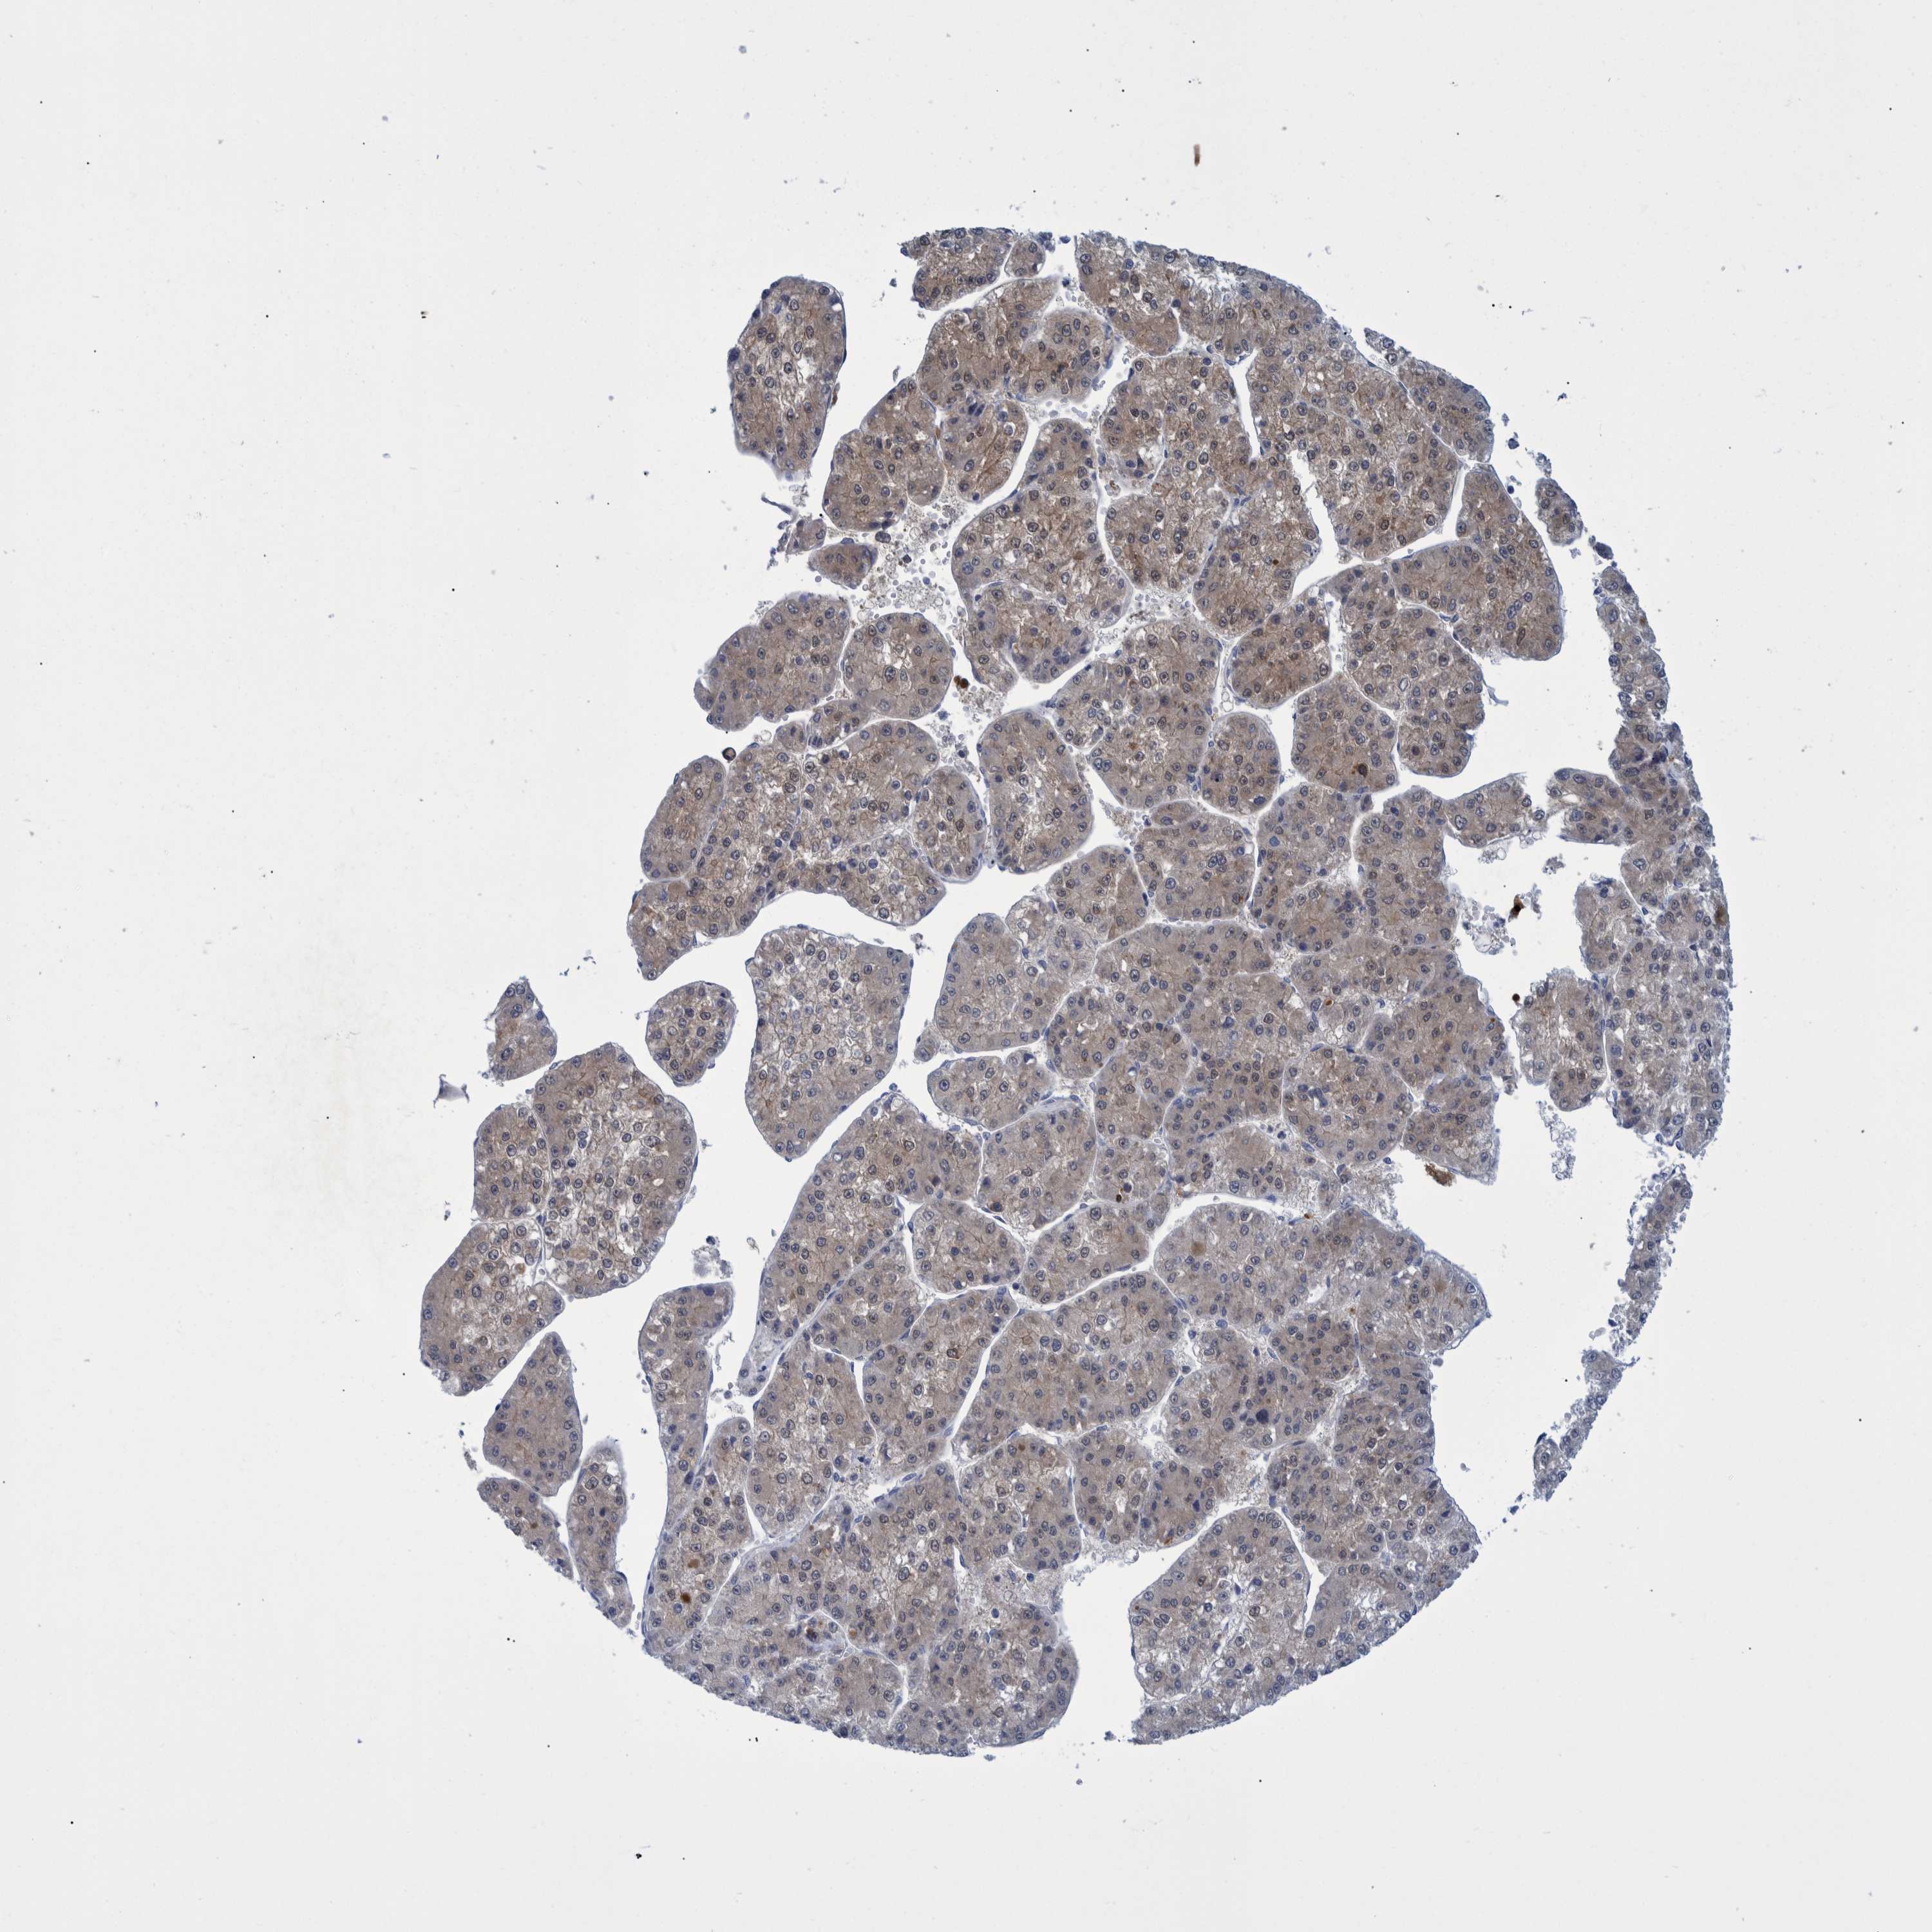

LIVER CANCER - Protein expressioni

A mouse-over function shows sample information and annotation data. Click on an image to view it in a full screen mode. Samples can be filtered based on level of antibody staining by selecting one or several of the following categories: high, medium, low and not detected. The assay and annotation is described here.

Note that samples used for immunohistochemistry by the Human Protein Atlas do not correspond to samples in the TCGA dataset.

Antibody stainingi

Antibody staining in the annotated cell types in the current human tissue is reported as not detected, low, medium, or high, based on conventional immunohistochemistry profiling in selected tissues. This score is based on the combination of the staining intensity and fraction of stained cells.

Each image is clickable and will lead to virtual microscopy that enables deeper exploration of all samples and also displays staining intensity scores, fraction scores and subcellular localization as well as patient and tissue information for each sample.

Antibody HPA023033

Antibody HPA023034

Staining

High

Medium

Low

Not detected

Intensity

Strong

Moderate

Weak

Negative

Quantity

>75%

75%-25%

<25%

None

Location

Nuclear

Cytoplasmic/membranous

Cytoplasmic/membranous,nuclear

Cholangiocarcinoma

Carcinoma, Hepatocellular, NOS